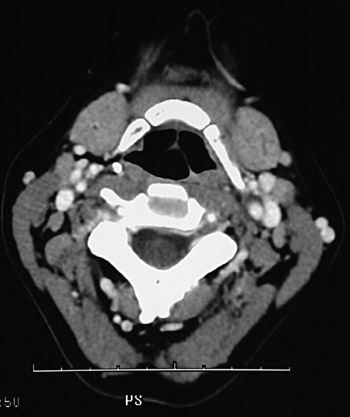

This is a normal axial head and neck CT scan demonstrating the hyoid bone and pharynx and submandibular gland and spinal canal and sternocleidomastoid muscle and internal jugular vein and external carotid artery and internal carotid artery.